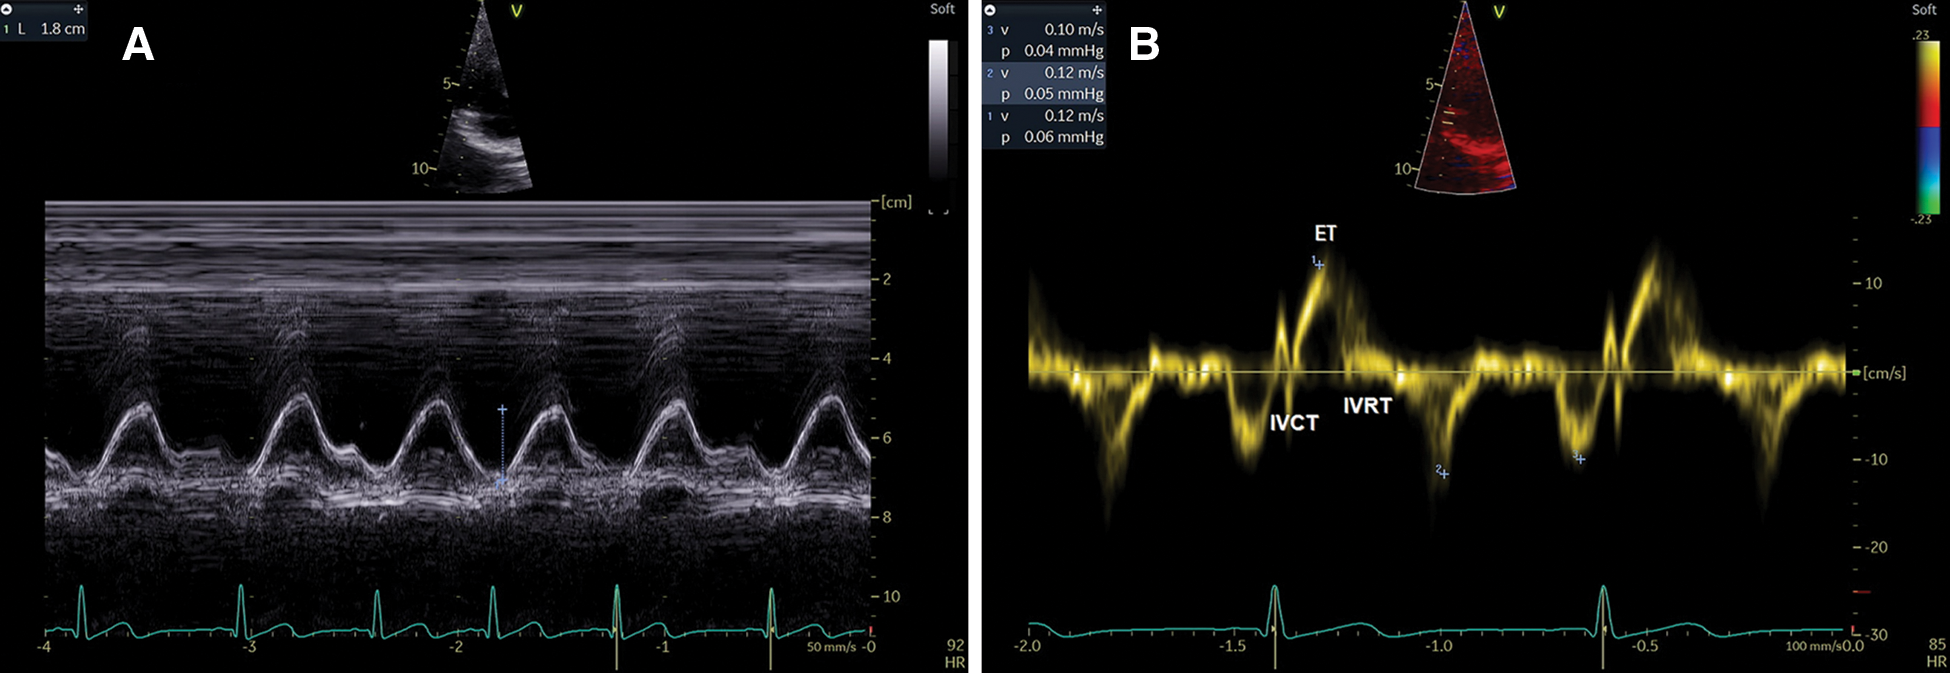

Transthoracic echocardiography (TTE) was performed for all children using the Vivid E9 machine (GE Vingmed Ultrasound N-3191, Horton, Norway). Children with ASD were examined before the procedure, as well as 24 h, 1 month, and 6 months after intervention. ASD and right chambers assessments were performed according to established criteria from the European and American Society of Echocardiography [16–20]. The Qp/Qs ratio was estimated by Doppler measurements of pulmonary and aortic stroke volume [17]. RA dimensions were assessed by RA major and minor diameters while RA area was estimated by planimetry “Figs. 1A–1C”. RV dimensions in the form of RV mid–cavity, RV longitudinal, and RV basal diameters were measured. RV function was assessed using right index of myocardial performance (RIMP) by tissue Doppler (TDI) and tricuspid annular plane systolic excursion TAPSE “Figs. 2A and 2B”. RV systolic pressure (RVSP) and mean pulmonary artery pressure (PAP) were measured. RA volume was calculated as follow: 8/3π (RA area2/RA major length) [16,19]. RA pressure was estimated by inferior vena cava (IVC) diameter and inferior vena cava collapsibility index (IVCCI) in a subcostal view.

Figure 1: (A) RA area, RA major, and minor diameters of a studied child from TTE apical-4 chamber view. (B and C) ASD size, and rims from TTE subcostal views

Figure 2: (A) Tricuspid annular plane systolic excursion (TAPSE). (B) Right index of myocardial performance by tissue Doppler (RIMP-TDI) (ET; Ejection time, IVCT; isovolumetric contraction time, IVRT; isovolumetric relaxation time) from TTE apical views